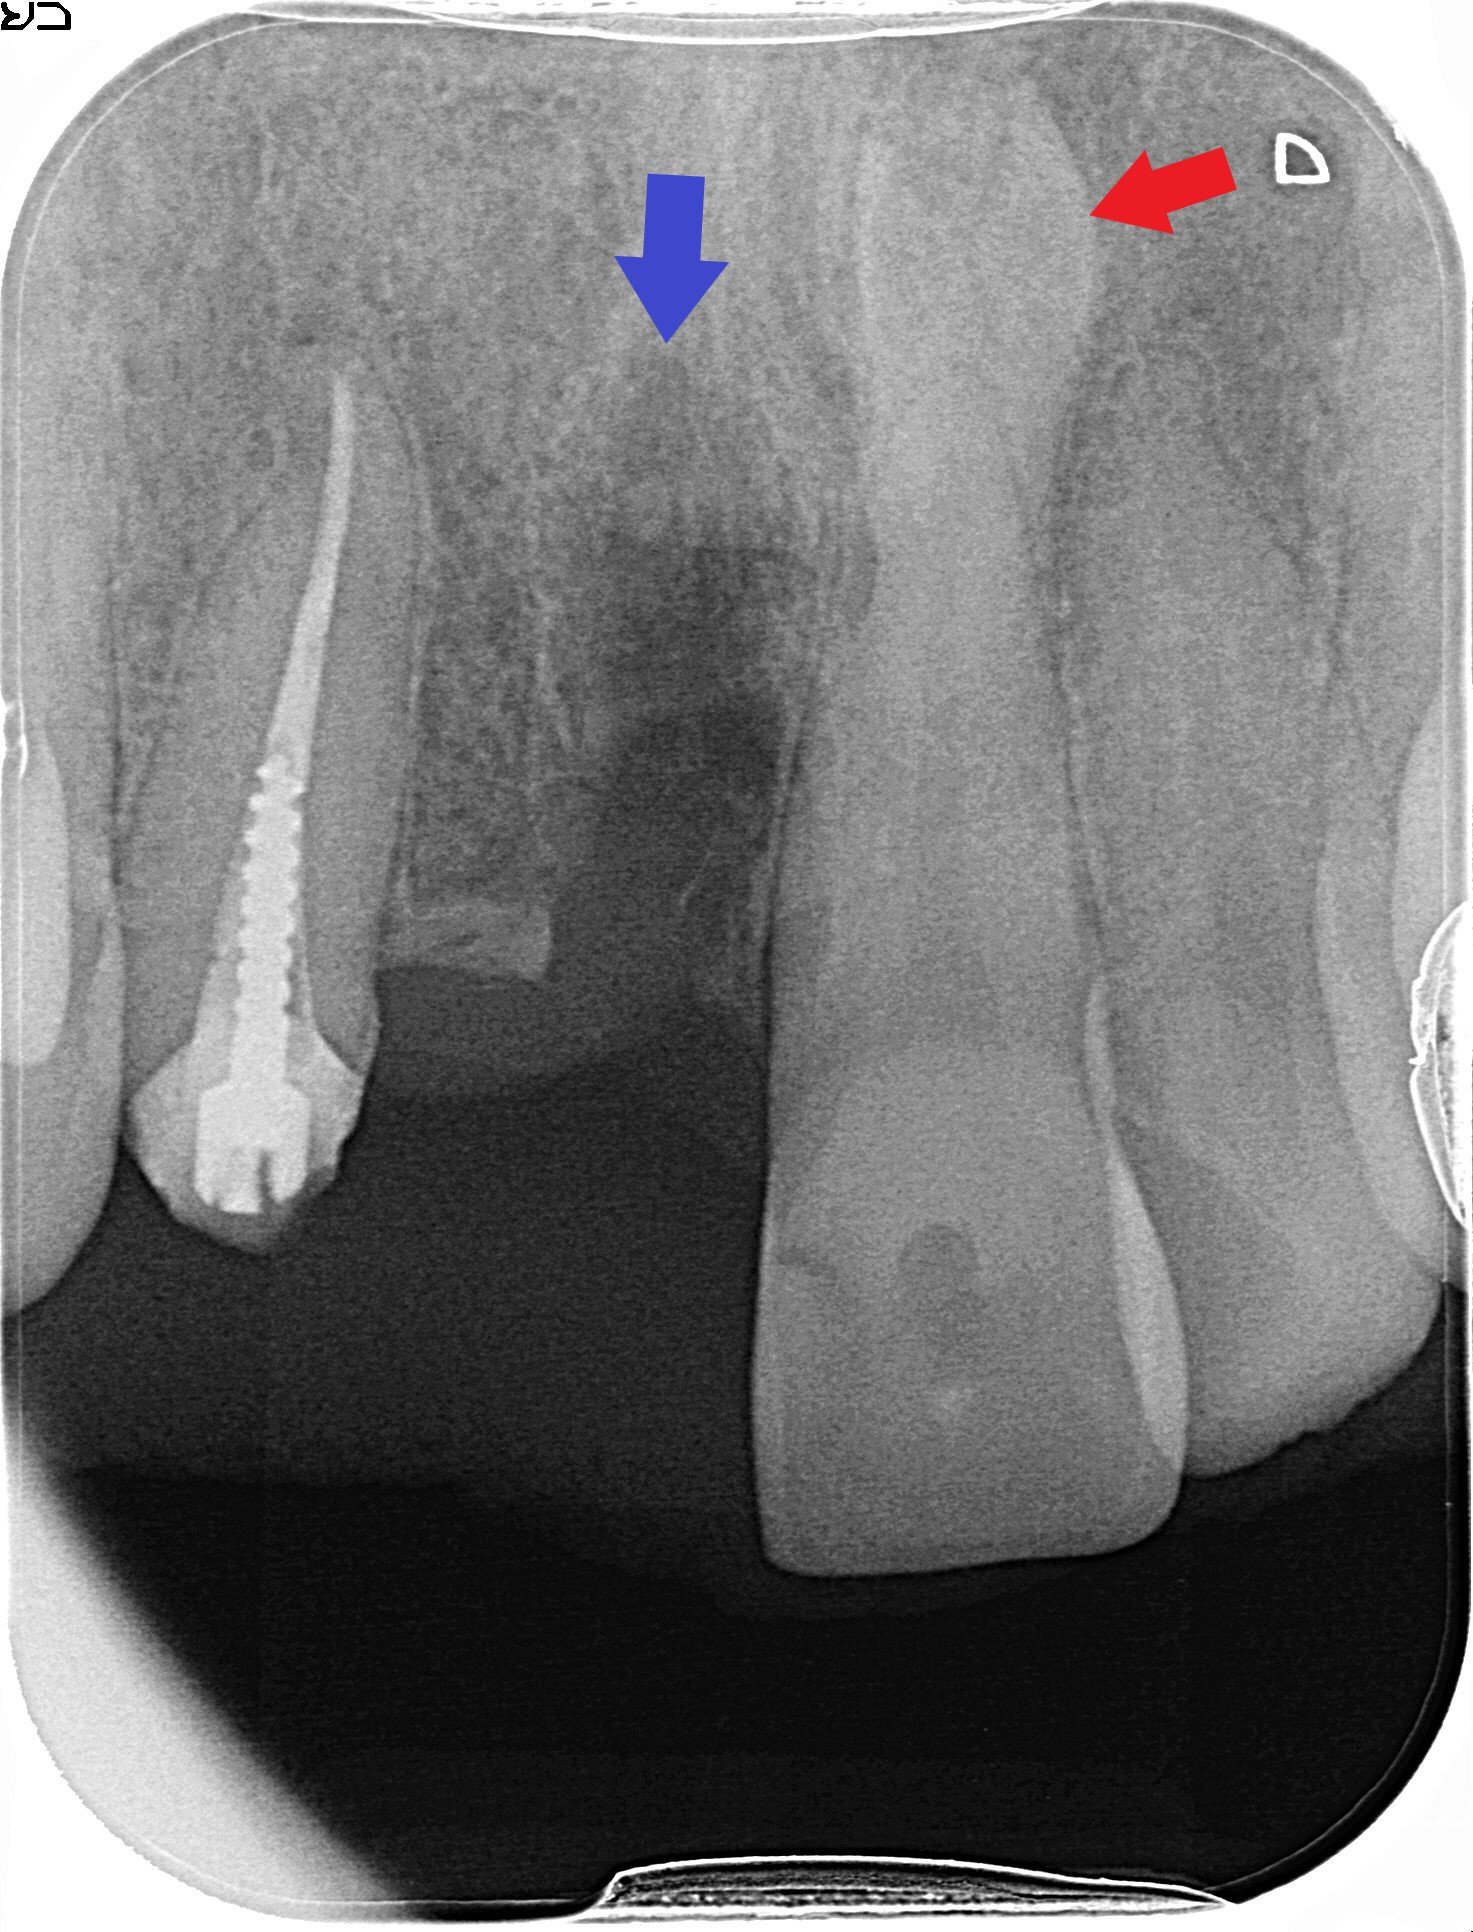

【治療計画と処置】

患者様は右上前歯にインプラント治療を希望されたため、仮歯下の1本の過剰歯(青色矢印)を抜歯しました。もう1本の過剰歯(赤色矢印)は、位置的に支障がないため経過観察としました。